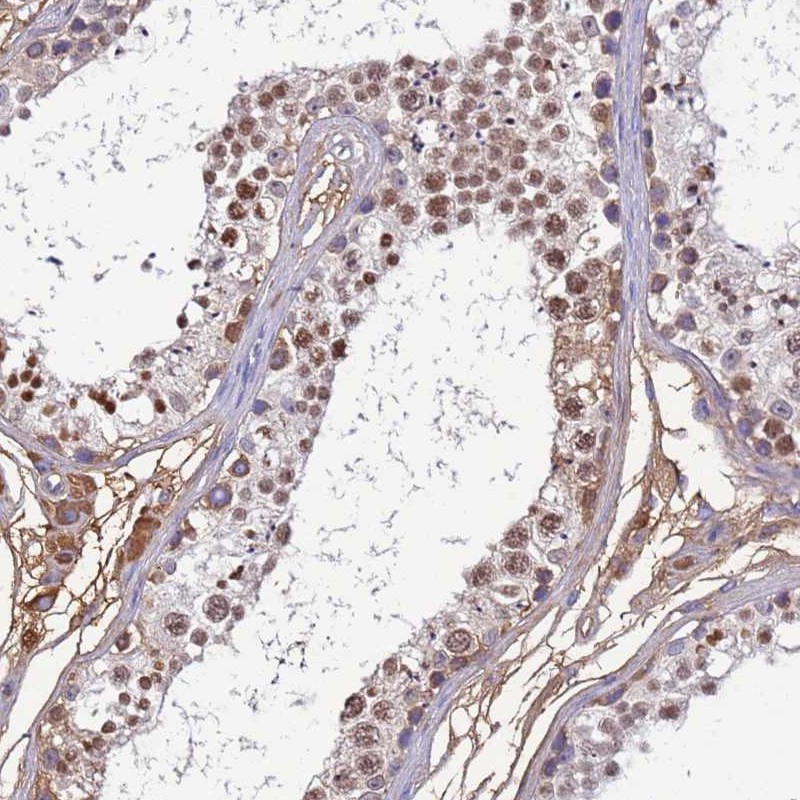

Immunohistochemical staining of human testis shows moderate cytoplasmic and nuclear positivity in cells in seminiferus ducts.